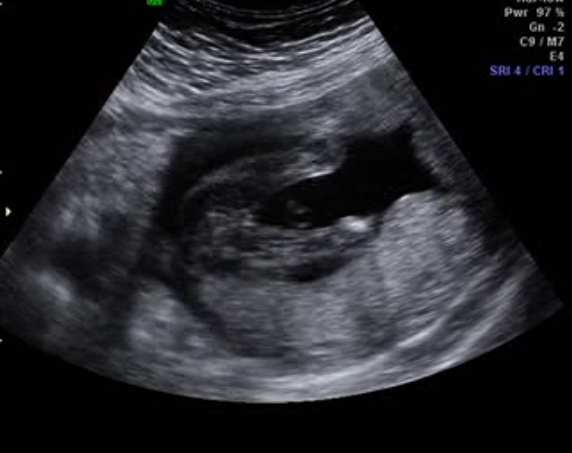

I have a picture here captured from the video, it's not the clearest pict in the world, so I will post a link to the video of my ultrasound as well.

I know what I think the baby is but I am so interested to hear what all of your guesses are.